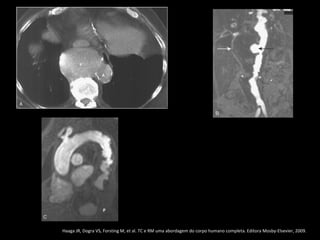

• Haaga JR, Dogra VS, Forsting M, et al. TC e RM uma abordagem do corpo humano completa. Editora Mosby-Elsevier, 2009 ..

• Haaga JR, Dogra VS, Forsting M, et al. TC e RM uma abordagem do corpo humano completa. Editora Mosby-Elsevier, 2009

Haaga JR, Dogra VS, Forsting M, et al. TC e RM uma abordagem do corpo humano completa. Editora Mosby-Elsevier, 2009.